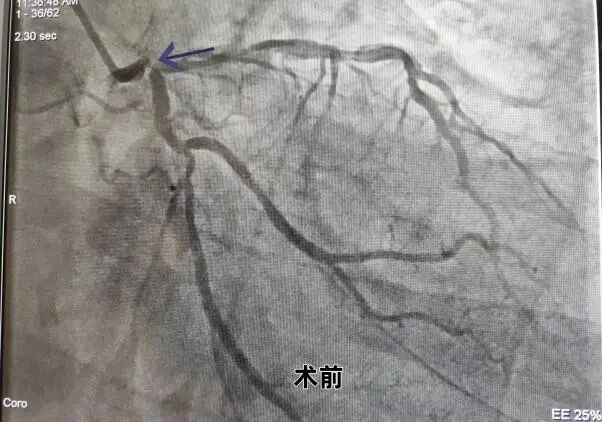

患者为65岁老年患者,因“反复胸痛20余天”入院,有高血压病史,有吸烟史。心电图:窦性心律,左心房扩大及左室肥大可能,入院后行冠脉造影检查:冠脉分布呈右优型;左冠及右冠走行区钙化影,左主干末端90%狭窄并累及前降支、回旋支开口,前降支开口-中段弥漫性狭窄,最窄90%,血流TIMI3级;回旋支开口80%狭窄,近-远段弥漫性狭窄,最窄75%,血流TIMI3级;右冠管壁欠规则,近段30%局限性狭窄,中段30%局限性狭窄,远段90%管状狭窄,后降支开口-近段50%局限性狭窄,中段50%局限性狭窄,血流TIMI3级。

面对如此复杂高危的冠脉病变,制定合理的治疗策略非常关键,患者造影结束安返病房。随后在中组部“组团式”帮扶专家游琼主任医师指导下,徐宗荣及杨力副主任医师介入团队逐帧仔细判读冠脉造影结果,再次熟悉临床资料,认为该患者SYNTAX评分34分,遂建议首选外科搭桥手术,但患者与家属不同意外科手术并要求介入治疗。基于患者病情危重,病变复杂,介入手术难度极大,手术风险极高,需强支撑大管腔指引导管处理,介入团队综合考虑了患者病情及经济因素后,获得患者及其家属知情同意,决定迎难而上,经我院介入团队充分讨论及评估,利用桡动脉无鞘技术,采用IABP保护下采用SKS术式,成功植入4枚支架,手术总共耗时2个多小时,整个手术过程顺利,术中无并发症,患者术后恢复良好,胸闷痛基本缓解,目前患者已康复出院。